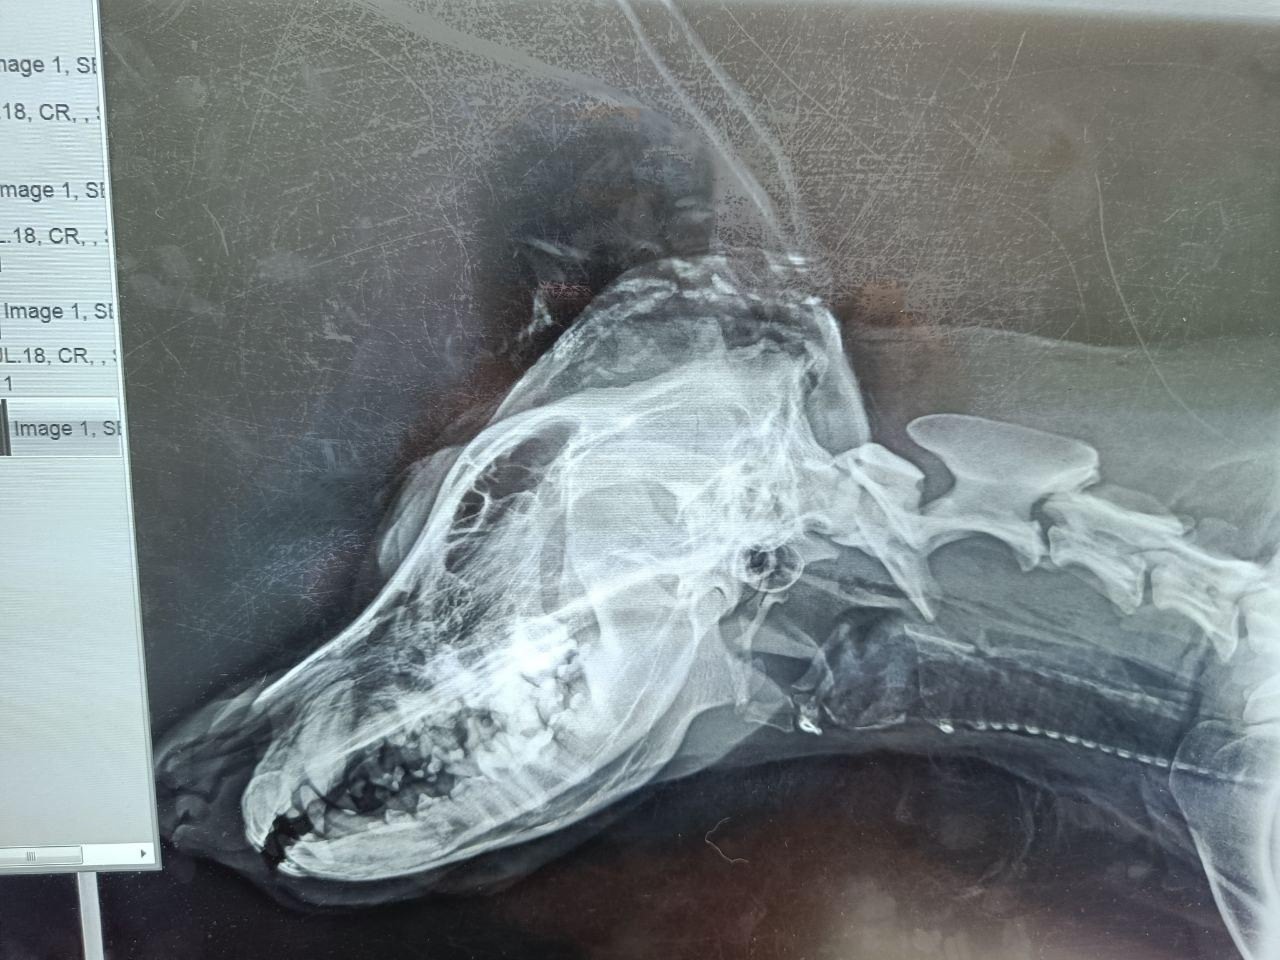

Овчарку назвали Абаном. Зоозащитники заявили, что ударить его могли топором – нашли «очень маленькие осколки». Сейчас, как говорят волонтеры, псу уже провели операцию.

«Врач подтвердил, что мозг остался незатронутым. Рана глубокая, но очищенная, инфекция отсутствует. Повреждение свежее, врачи предполагают, что оно случилось совсем недавно. Поставили сразу три дренажные системы. Но ситуация остается сложной: сагиттального гребня больше нет, прогнозы докторов пока предельно осторожны», – сообщили волонтеры из Шалинского у себя в соцсетях.